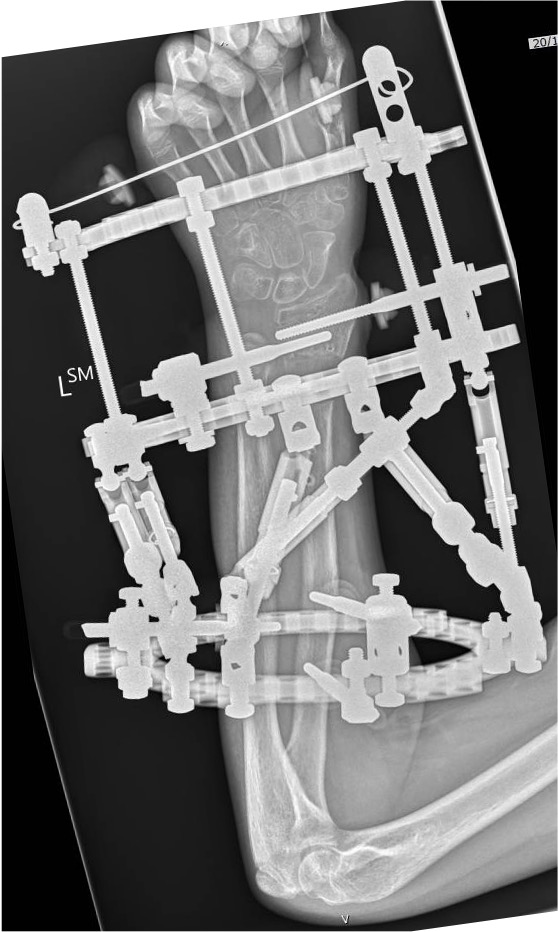

Options

MUA

MUA + K wire stabilisation

Indications K wire

Remanipulation of metaphyseal fracture

Instability

Associated with supracondylar fracture

Technique

Avoid physis if able in metaphyseal fracture

- dorsal Kapaji technique

- can use this technique laterally